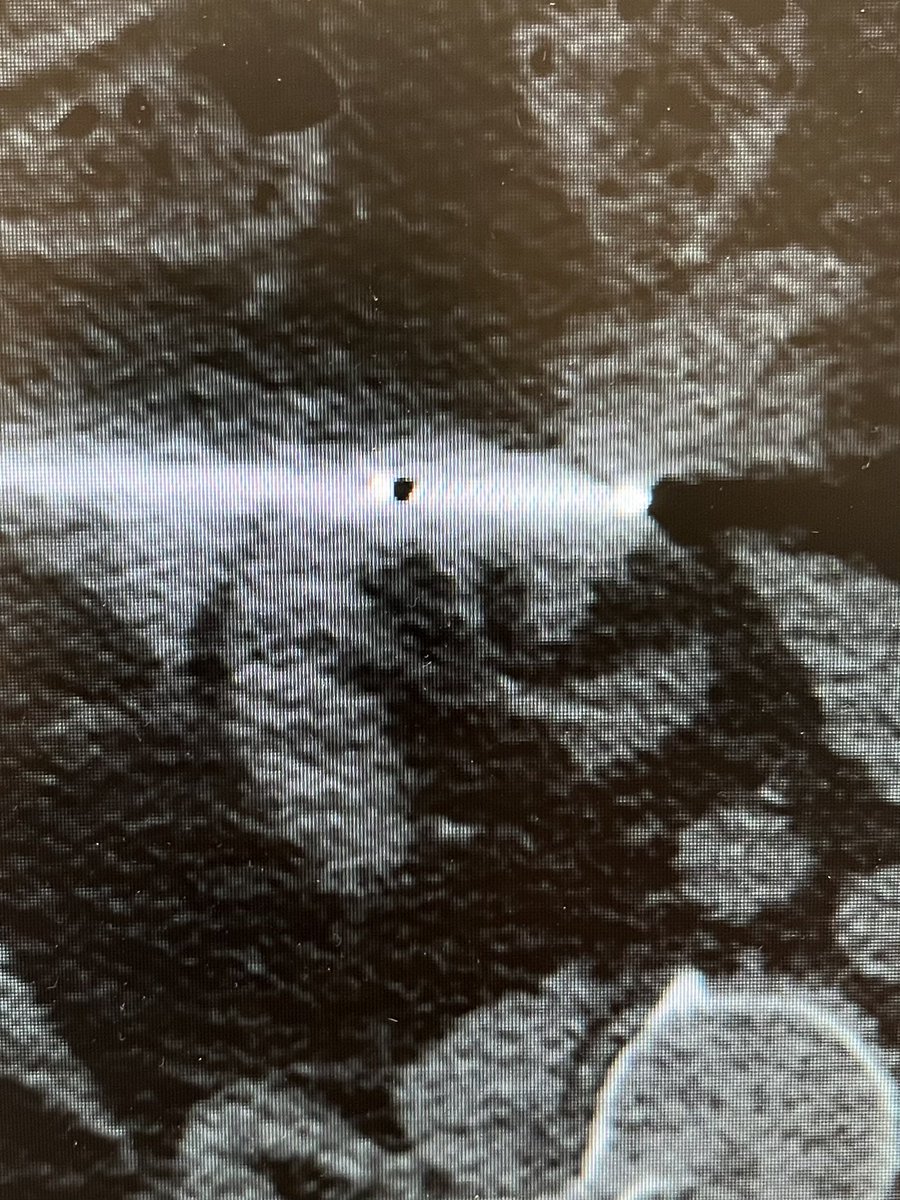

One of the 1st studies in healthcare using @HoloLens 2, supported by @RSNA. #AugmentedReality guidance improves procedure times and radiation dose. Med students also instantly elevated to #IRAD attending level! @dotter_IR @Penn_IR @PigiLab @SIRRFS rdcu.be/b9p98